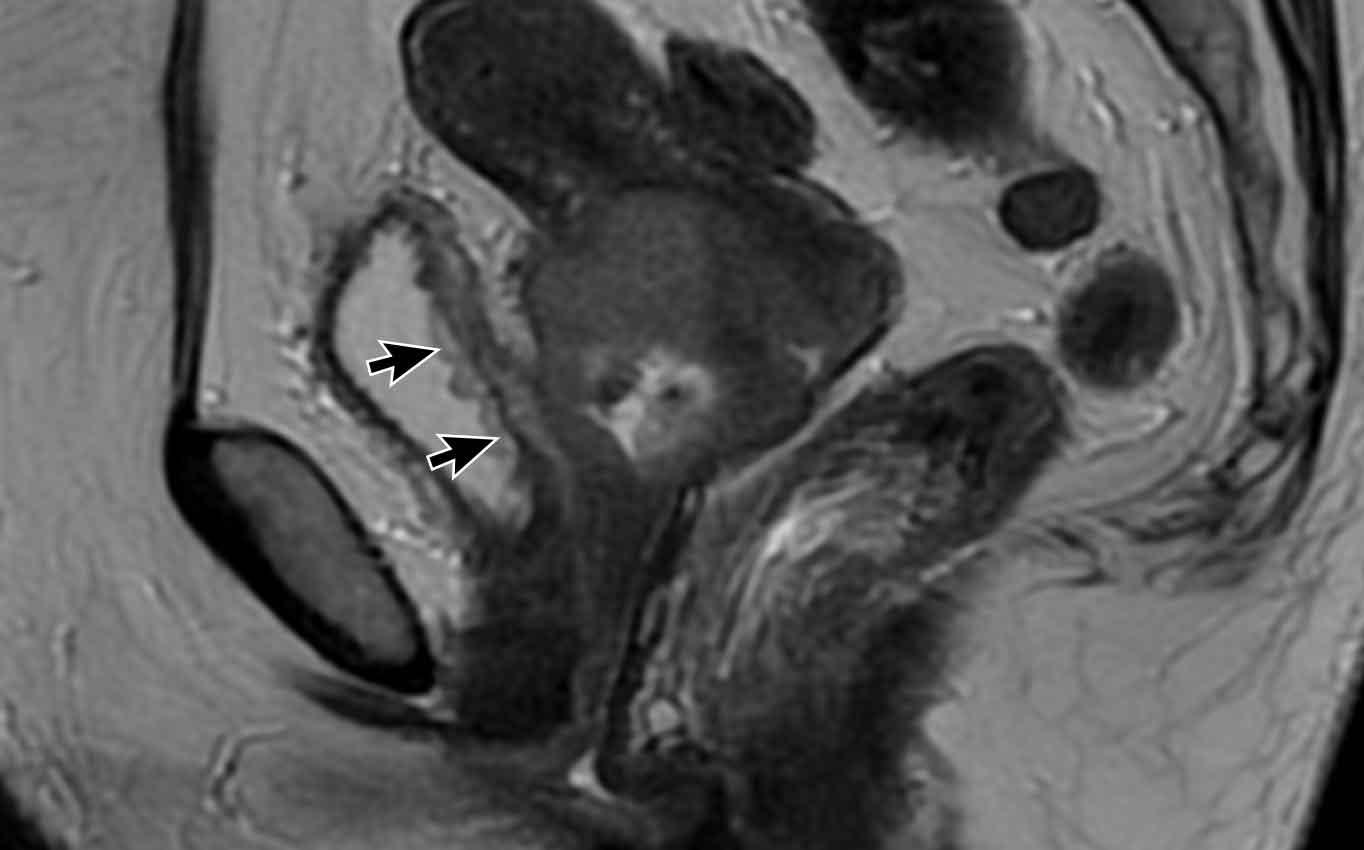

Bẫy chẩn đoán

– Giãn rộng so với xâm lấn

Ví dụ này cho thấy một khối u lớn làm giãn rộng cổ tử cung.

Lưu ý rằng không có xâm lấn thực sự vào vùng cạnh cổ tử cung vì vòng mô đệm giảm tín hiệu của cổ tử cung hoàn toàn còn nguyên vẹn như được chỉ ra bởi các đầu mũi tên.